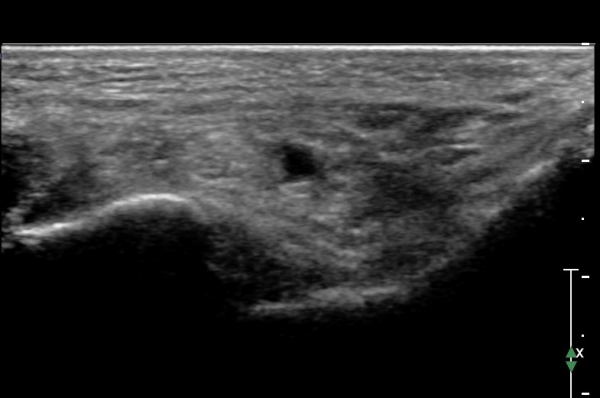

Å½ÃËÁö¸¦ Á¶±Ý ´õ ¸»´ÜÀ¸·Î À̵¿ÇÏ¿© sustentaculum  tali À§Ä¡¿¡ ¿À´Ï À幫Áö±¼±Ù°Ç ÁÖº¯¿¡ ¼ö¾×Àú·ù°¡

°üÂûµÇ°í ³»Ãø Á·Àú½Å°æÀÇ ÀüÀ§°¡ °üÂûµÊ. sustentaculum  tali Ç¥Ãþ¿¡ À§Ä¡ÇÑ ÀåÁ·Áö±¼±Ù°ÇÀº

ºñµî¹æ¼º(anisotropic) ÀΰøÀ½¿µ(artifact)¿¡ ÀÇÇÏ Àú¿¡ÄÚ µ¢¾î¸®·Î °üÂûµÊ(»çÁø 3).